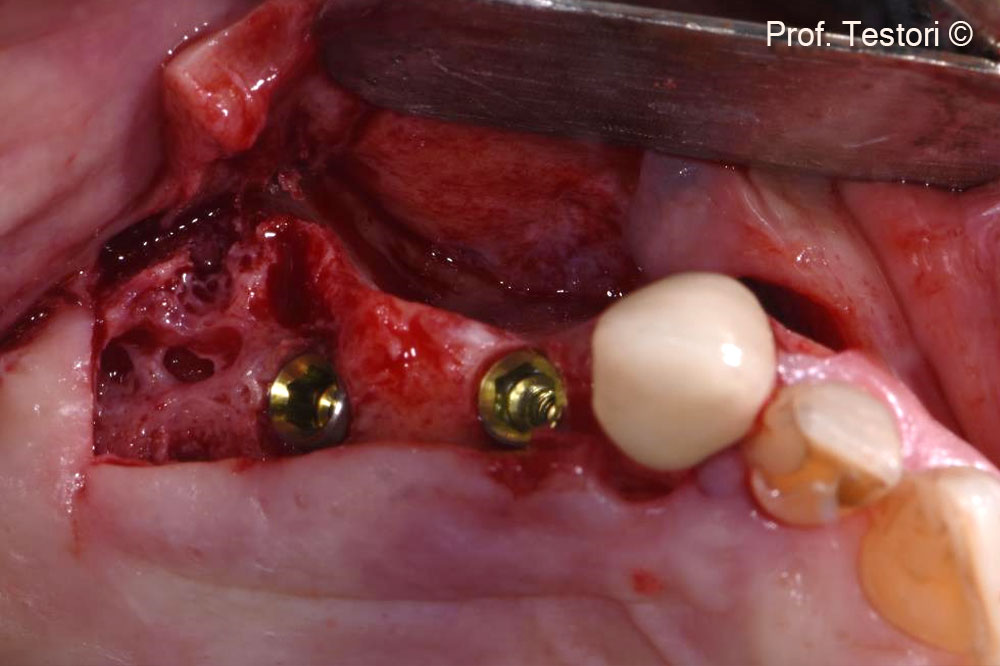

Clinical view of the defect.

Occlusal view of the horizontal bone defect around the dental implants